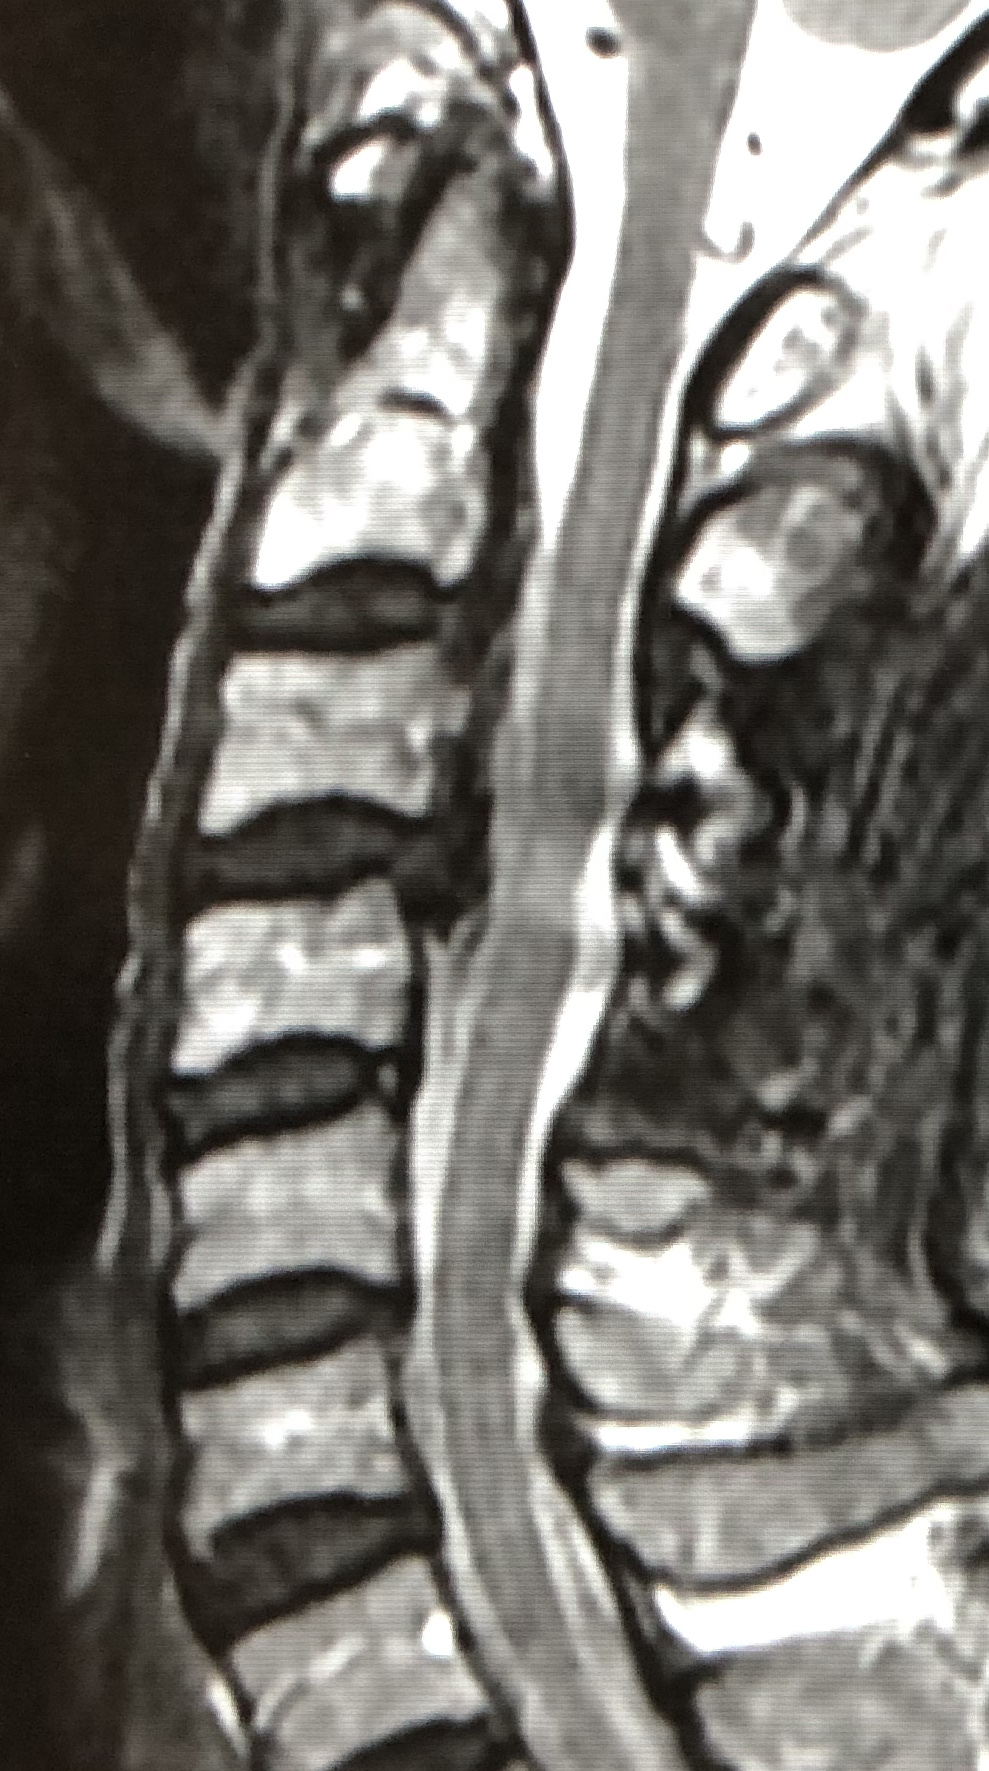

頚部脊柱管を後方から拡大し、脊髄の圧迫を除く手術方法です。

手術後は脊柱管が明らかに拡大しています。

| 術前 | 術後 |